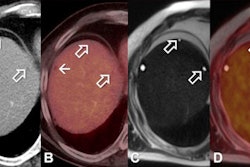

Screening MBI included an intravenous injection of 8 mCi of Tc-99m sestamibi, with bilateral two-view MBI performed with a dual-head cadmium zinc telluride-based gamma camera.